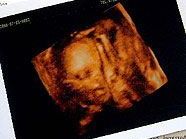

“Wenn die noch nicht mal so was unkompliziertes wie Dokumentation auf die Reihe kriegen, lässt das nichts Gutes für die Zukunft verheißen”, sagte der Mann, der anonym bleiben wollte. “Wir waren am Boden zerstört. Wir hatten unsere Embryonen schon durch das Mikroskop gesehen.”

Die Klinik räumte den Fehler, der bereits 2004 passierte, am Mittwoch ein und entschuldigte sich bei dem Paar. In Großbritannien dürfen Embryonen jahrelang gelagert werden. In diesem Fall habe es sich um ein Irrtum der Apparatur gehandelt, sagte ein Sprecher der Uniklinik. Es sei kein menschlicher Fehler gewesen. Das war nicht die einzige Panne bei einer künstlichen Befruchtung.

Erst am Wochenende war bekanntgeworden, dass dieselbe Uniklinik in Cardiff im Labor Embryonen verwechselte. Ihr Embryo sei vor zwei Jahren irrtümlich in die Gebärmutter einer anderen Frau gepflanzt worden, sagten die Eltern dem Boulevardblatt “Sunday Mail”. Als die Ärzte den Fehler bemerkten, hätten sie der Patientin eine Abtreibungspille gegeben, die die Schwangerschaft beendete. Die Klinik habe sich für den Fehler entschuldigt und zahlte 25.000 Pfund Entschädigung (30.000 Euro). Mit dem Geld will das Paar einen weiteren Versuch starten.